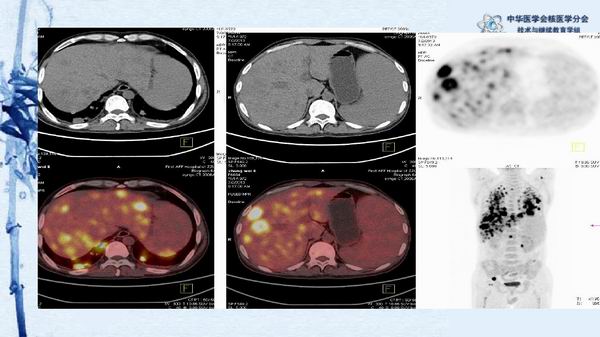

病例49:PET-CT显像诊断淋巴瘤相关噬血细胞综合征一例-【CSNM继教学组】程兵 郑州大学第一附属医院